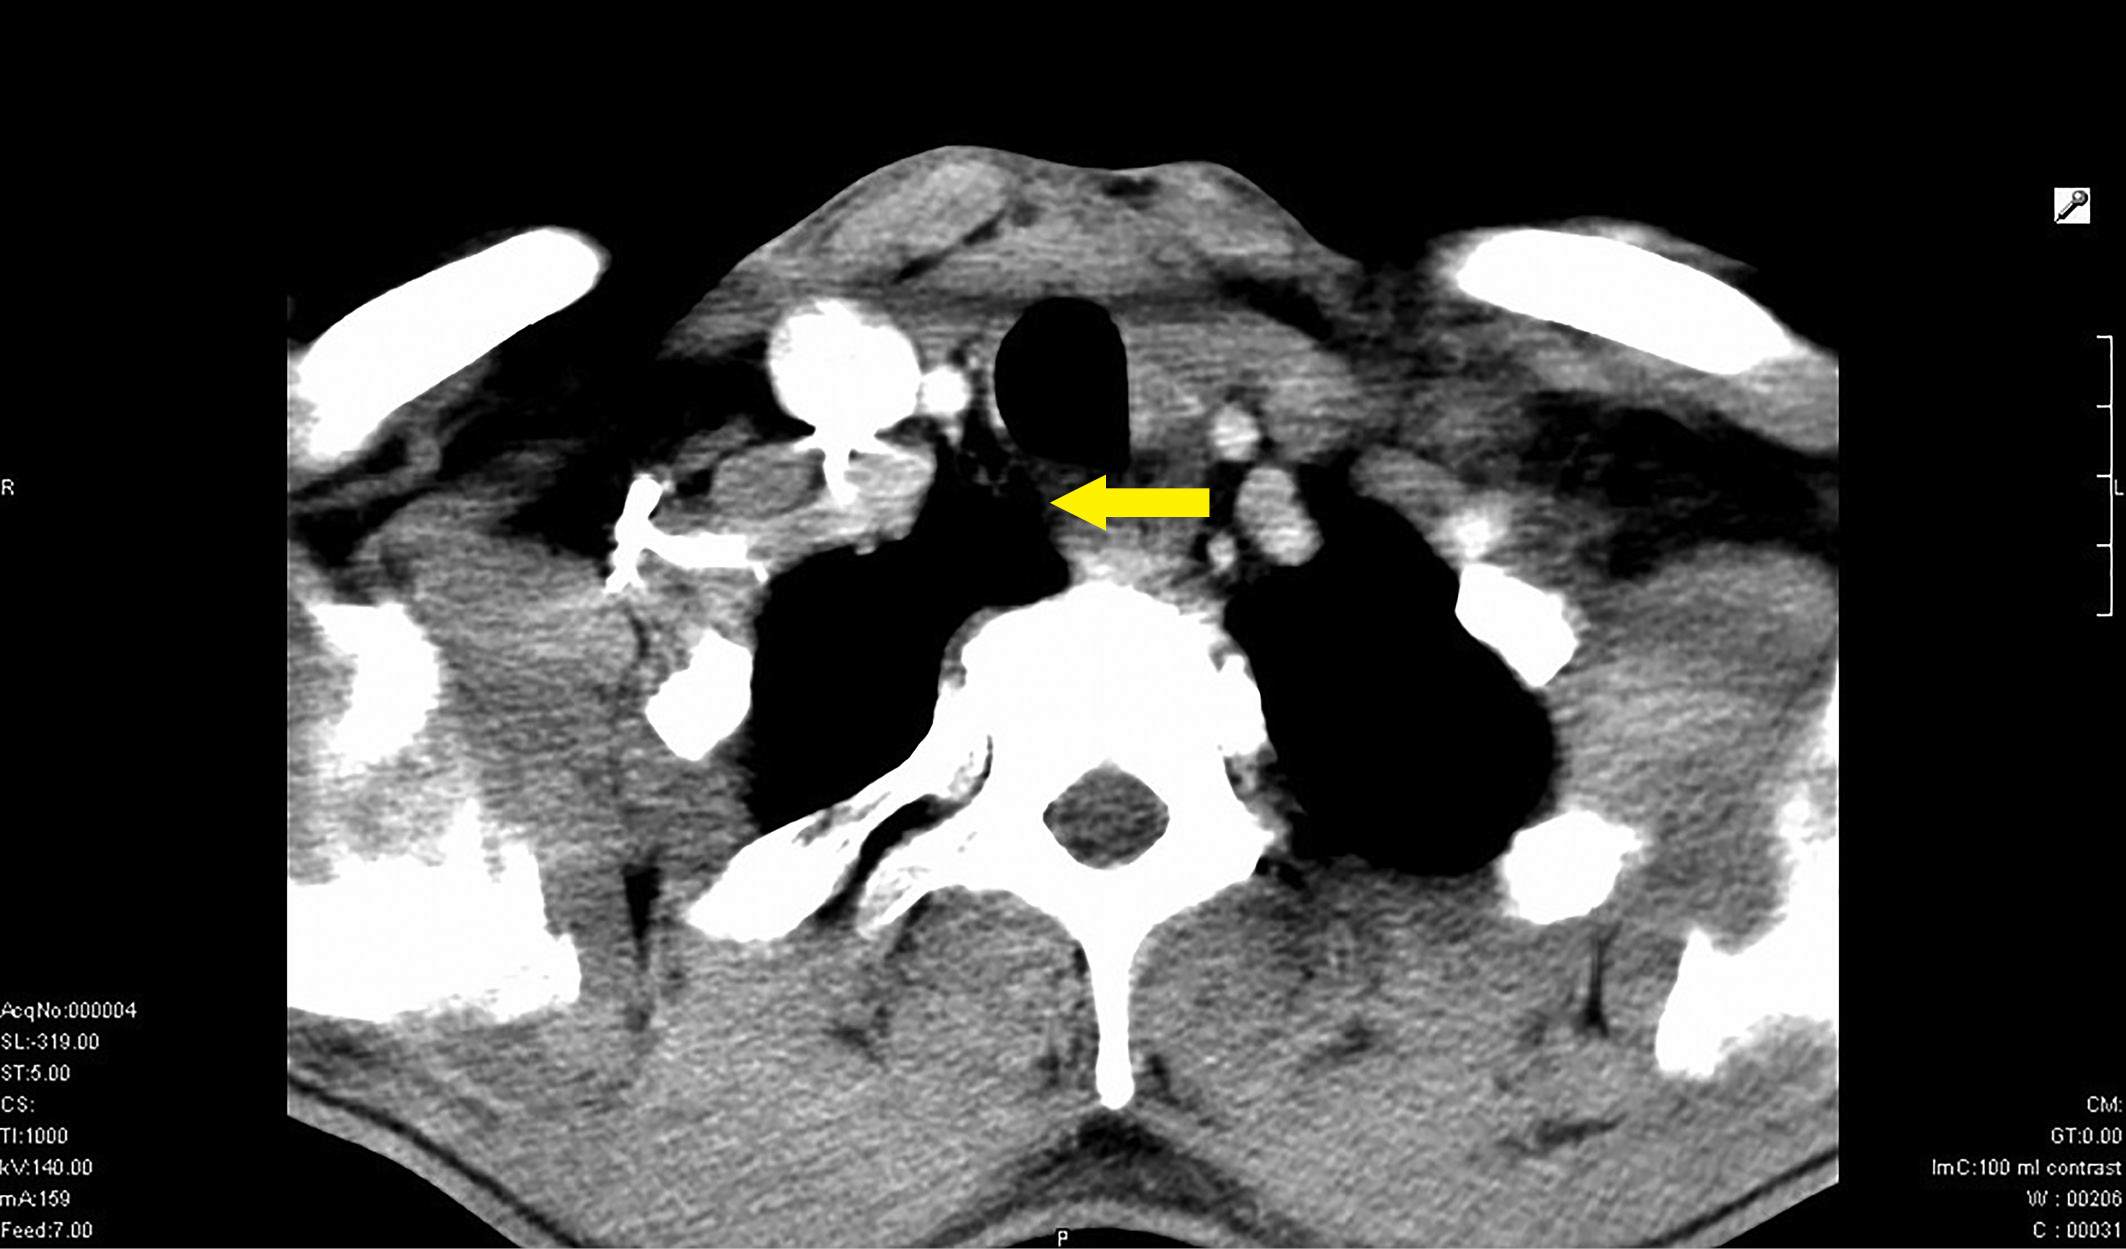

4. Рисунок 4. Больная Ш. Компьютерная томография опухоли щитовидной железы с врастанием в трахею. | |